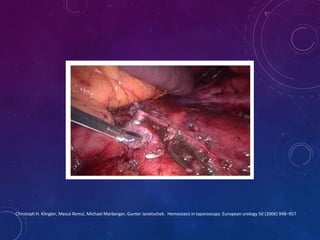

Hemostasia en laparoscopía

Hemostasia en laparoscopía

Hemostasia en laparoscopía

Hemostasia en laparoscopía